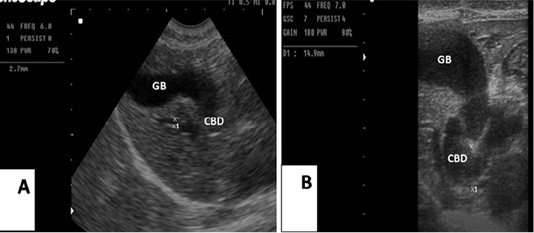

(A): Sagittal ultrasonographic image of gallbladder (GB) and common bile duct (CBD) in dog before surgery, 2.7mm; (B): the image showed the maximum dilatation of gallbladder (GB) and common bile duct in the 2nd week after ligation, 14.9mm.